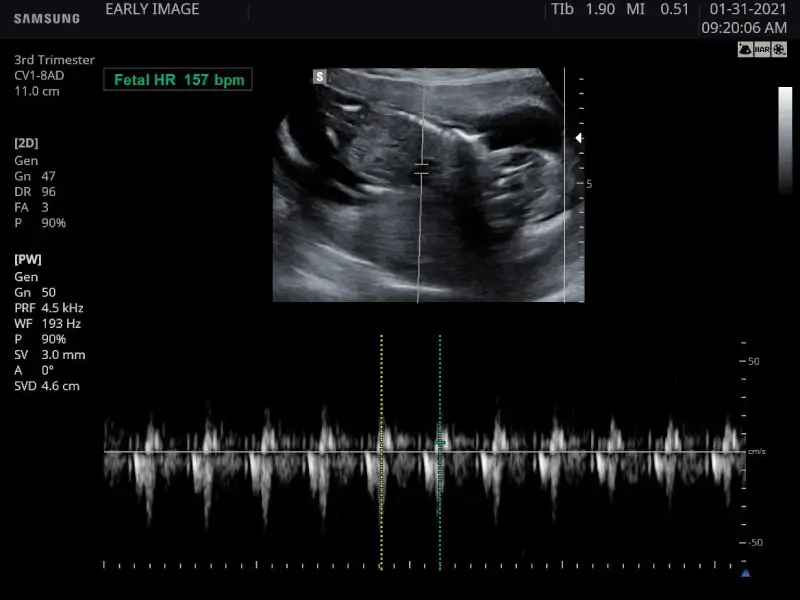

We will also listen to and measure its heartbeat, check your due date and then take some awesome images and moving clips which we will transfer directly to your phone at the end of your scan

Check baby’s hearbeat